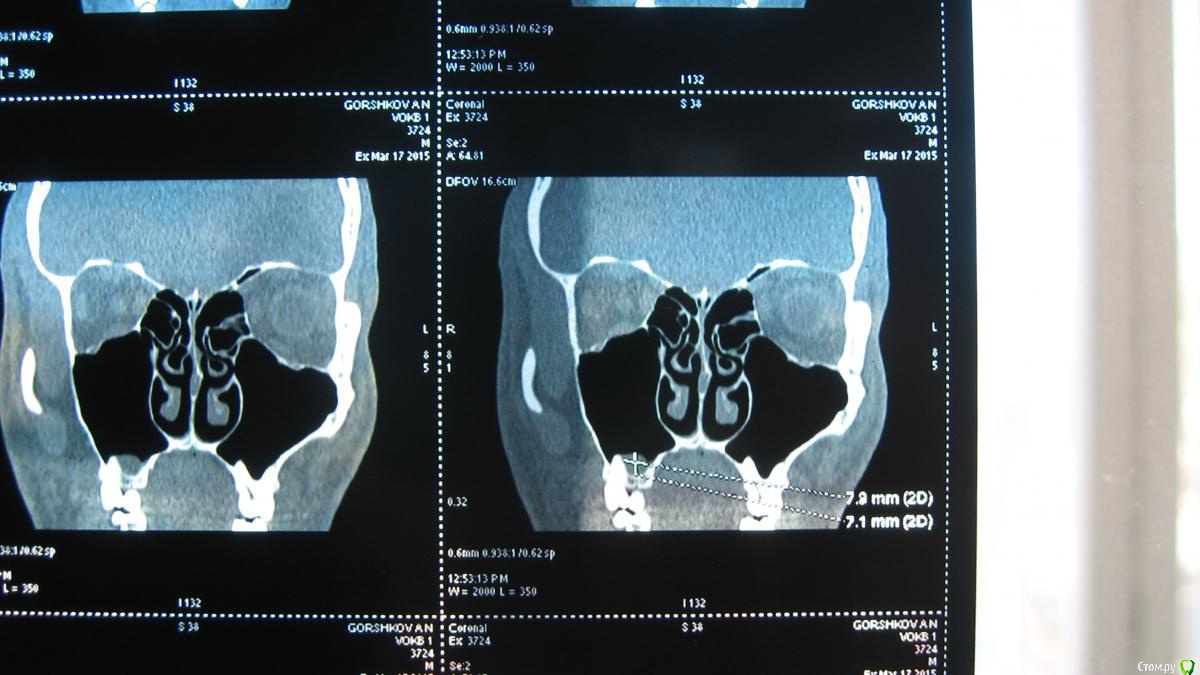

sasha35 Опубликовано 21 марта, 2015 Поделиться Опубликовано 21 марта, 2015 Здравствуйте. Осенью 2014 года лечил 4 зуб вверху. На 2 день после установки пломбы была боль, которая прошла через несколько дней. Со временем обнаружил, что больно нажимать на верхушку корня. Сам по себе не болит.Сделал снимок зуба, сходил к стоматологу. Он сказал, что плохо запломбирован канал. Я отказался вскрывать зуб. Сейчас появилась необходимость сделать СКТ ППН (для испр. носовой перегородки). Обнаружена киста в/ч пазухи, с той стороны где этот зуб(7*8мм) Сделал панорамный снимок челюсти, пошел к челюстно-лицевому хирургу. Он на снимке ничего не нашел. Тоже сказал, что зуб плохо запломбирован и возможно идет воспаление. Кисты на снимке нет. Может такое быть, на СКТ киста есть, а на рентгене нет? Выходит либо кистане связана с зубом, либо на СКТ воспаление показало как кисту? К кому мне обращаться? Ссылка на комментарий

sasha35 Опубликовано 22 марта, 2015 Автор Поделиться Опубликовано 22 марта, 2015 СКТ и рентген зуба. Панорамного снимка нет. Ссылка на комментарий